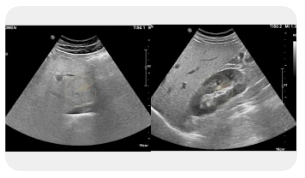

🧫 왼쪽 옆구리 통증 신장

신장은 체내 노폐물을 걸러주는 중요한 기관으로, 이상이 생기면 왼쪽 옆구리 통증을 유발할 수 있습니다. 요로결석의 경우에는 갑작스럽고 심한 통증이 나타나며, 신우신염은 감염으로 인해 열과 함께 통증이 동반됩니다. 신장 결석은 통증이 소변 볼 때 심해지는 특징이 있고, 경우에 따라 혈뇨가 나타나기도 합니다. 통증이 심하거나 발열이 함께 있다면 반드시 병원 진료를 받아야 합니다.